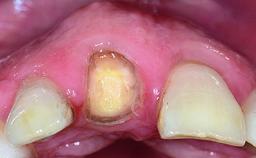

Replacement of an Ankylosed Central Incisor with a Gingival Recession: Tooth Extraction with Socket Grafting and Late Implant Placement with Simultaneous Contour Augmentation

In 2008, a healthy 15-year-old female, non-smoking patient presented at our clinic with a major esthetic problem of tooth 21. Her dental history revealed that the tooth had been avulsed by trauma years before. As a result, the replanted and temporarily splinted tooth had ankylosed and was in severe apical malposition. The ankylosed tooth exhibited a significant gingival recession that disturbed the patient greatly. Due to the patient’s low age and with her skeletal growth not completed, periodic follow-up visits were scheduled to monitor the situation until the patient was old enough for implant therapy.

Bone Augmentation Horizontal|Simultaneous|Staged|Vertical

Augmentation Materials Autogenous chips|Xenogenous|Membrane

Bone Volume Deficient vertically or deficient vertically AND horizontally